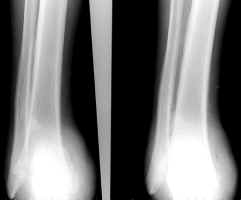

These images show an amputation through the calcaneal-cuboid and talo-navicular joints

(Chopart level).

Selected images of different patients showing the Chopart amputation.